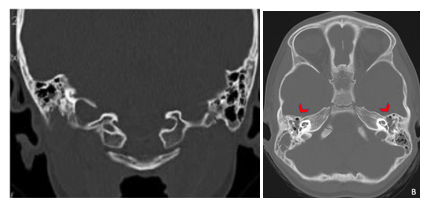

A subsequent CT scan of the brain, complete abdomen, and thorax showed soft tissue lesions that were homogeneous, well defined, and exhibited mild enhancement with contrast, eroding and altering the morphology of the skull cortex without infiltrating the brain parenchyma (Figure 2A & 2B). Additionally, multiple lytic lesions were identified in the sphenoid bone and vertebral bodies of C2, C3, and C5 vertebrae. Thoracic CT revealed lytic lesions in the vertebral bodies of T1, T3, T4, T6, and T7, along with pathological fractures of T5 and T9 (Figure 3A & 3B). Given the extensive bone involvement, the possibility of aggressive systemic disease was considered, including LCH, neuroblastoma, and metastatic rhabdoid tumors. Definitive histopathological examination of the previously biopsied tissue, complemented by immunohistochemistry, confirmed the diagnosis of Langerhans cell histiocytosis (LCH). Immunohistochemical staining was positive for S-100, CD68, PD-L1, and CD1a, which further confirmed the diagnosis. Due to the patient developing bilateral ear discharge, a mastoid CT scan was performed. The scan showed a loss of normal mastoid morphology with bony erosion caused by homogeneous soft tissue lesions bilaterally (right mastoid: 2.9 x 1.8 cm, left mastoid: 3.4 x 2.3 cm) (Figure 4A & 4B). These findings are consistent with the systemic spread of LCH, which affects the temporal bones.

Figure 2A&2B Cerebral CT scan of the patient- Evidence of soft tissue lesions, homogeneous, with well-defined borders, showing mild contrast enhancement in the occipital and frontal regions.

Figure 4A&4B Mastoid CT of the patient revealed total opacification of the remaining mastoid air cells and loss of morphology of both mastoid portions of the temporal bone.